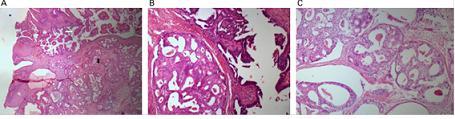

Figura 2. (A) Siringocistoadenoma papilìfero (flecha blanca). Debajo de èsta region desarrollo de adenocarcinoma (flecha negra). (B) Siringocistoadenocarcinoma papilìfero H&E_20. (C) Areas de adenocarcinoma.

(H&E_20)

El siringocistoadenocarcinoma papilìfero (SCACP) es una forma rara de adenocarcinoma de la piel. El SCACP es una forma maligna de siringocistoadenoma papilífero (SCAP). Ocasionalmente, se presentan casos de SCAP como lesiones nodulares o símil-placas, pero rara vez se presenta el SCACP. Puede desarrollarse de un SCAP o de un nevo sebáceo de Jadassohn. Existen 13 casos descriptos en la literatura de SCACP. En éste artículo se reporta y discute el 14 caso de SCACP en el cuero cabelludo de un hombre de 67 años.Caso ClínicoSe presenta un hombre de 67 años con una lesión nodular de 4-2-2cm, ulcerada en la región occipitotemporal del cuero cabelludo (fig 1, izquierda). Los antecedentes revelan que estaba hinchada la región y era pruriginosa desde la infancia. La ulceración apareció 6 meses antes de la admisión. Se realizó biopsia incisional, con diagnóstico de lesión epitelial maligna. Aunque la biopsia incisional reveló un SCAP, la apariencia clínica de la lesión era maligna, por lo que se decidió tratarla como una lesión maligna. Se extirpó con 2 cm de márgenes quirúrgicos, preservando el periostio y se utilizó un injerto de piel de la piel del muslo para reconstruir el defecto (fig 1, derecha). El exámen histopatológico reveló la contraparte maligna del diagnóstico previo. En la porción epidérmica del tumor, estaba presente una papilomatosis irregular. Se observaron invaginaciones formadas por epidermis y estructuras papilares en la luz. Se observaron zonas de transformaciones malignas entre las estructuras papilares. Se encontraron áreas de adenocarcinoma que involucran generalmente estructuras sólidas y cribiformes con invaginaciones dérmicas profundas (fig 2). No hubo signos de recurrencia ni metástasis por 2 años luego de la cirugía. Se observaron invaginaciones epidérmicas a través de niveles dérmicos profundos con extensiones papilares en la luz.

Histopatológicamente, el SCACP y SCAP demuestran invaginaciones papilomatosas irregulares delimitadas por un epitelio de 2 membranas en la que la membrana luminal está compuesta por células columnares y pequeñas células cuboides en vecindad con el estroma. Las células plasmáticas y la infiltración de linfocitos del estroma, especialmente en las proyecciones papilares, es otra característica de observar. Por otra parte, la atipía celular y nuclear, pérdida de polaridad, proliferaciones de células neoplásicas interrumpiendo la organización de las membranas indican SCACP.